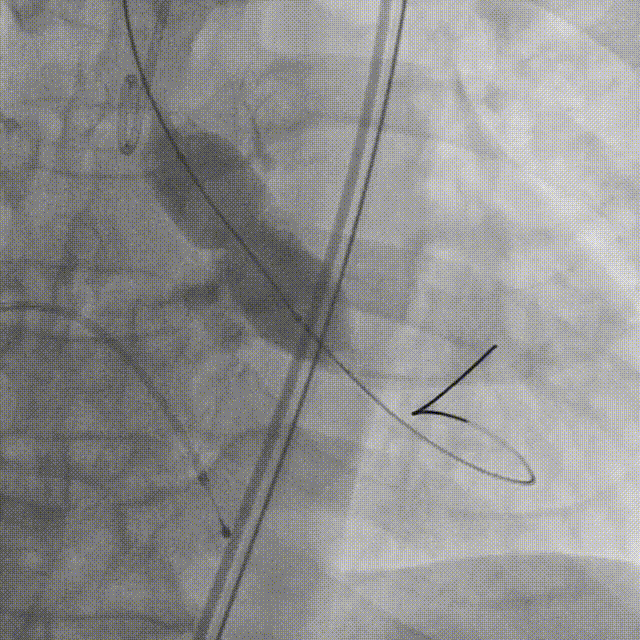

精准释放角度:左右冠窦重叠。

左右窦重叠角度可以清楚显示无冠窦,维持冠窦平面对齐,拉长左室流出道的视图,减少或去除医生的视差,以精准评估瓣膜植入深度。